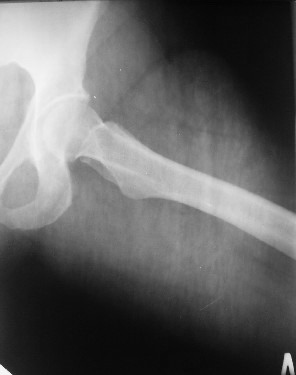

Уважаемые коллеги! Хотел-бы обсудить интерессный, на мой взгляд, случай.На консультацию пришла женщина 45 лет с отводящей контрактурой правого бедра.

Из анамнеза: в ноябре 2002г. оступилась,упалана трап самолета (на верхней площадке, сразу при выходе из салона) на правый тазобедренный сустав, а затем - вниз на землю на ноги и ягодицы. Потеряла сознание от боли. Доставлена в больницу по месту жительства, лечилась консервативно с диагнозом кокцигодиния.На рентгенограмме от 27.11.02г. вывиха копчика не определяется (снимок идентичен представленной R-грамме от28.11.03г., кроме этого есть нормальная R-грамма копчика в боковой проекции).Через три недели стала ходить, но привести правую ногу в тазобедренном суставе не могла. Сейчас ходит отведя кнаружи правое бедро и голень, как ножку циркуля (фото 1). Неврологических нарушений нет. По просьбе врачаможет на 30-40 секунд поставить ноги вместе (фото 2). При этом испытывает сильную тянущую боль и ощущение "вывернутости" в правом тазобедренном суставе. Эти ощущения заставляют вновь отвести бедро. В положении лежа разогнуть бедро полностью не может из-за болей в ягодичной мышце (фото 3). Сгибание также ограничено из-за болей (фото 4). Отведение в положении лежа возможно в том же объеме, что и стоя (фото 5). Заподозрен старый разрыв правого крестцово-подвздошного сочленения.Выполнено R-исследование и КТ(в приложении). По-поводу деформации лонного сочленения выяснен гинекологический анамнез. Роды одни, нормальные в 22 года. Из роддома выписана на 8 сутки, нарушения походки не было, R-графия таза не проводилась. Вопросы на обсуждение: 1. Диагноз либо алгоритм дальнейшего обследования. 2. Лечебная тактика (в первую очередь возможность и целесообразность оперативного лечения).

Уважаемый Юрий Алексеевич, сделаны ли пациентке более дистальные срезы КТ с захватом области тазобедренного сустава? Учитывая давность травмы, могли присоединиться и дистрофические процессы в субхондральной кости головки и впадины. Изменения в капсуле будут хорошо видны на УЗИ, особенно в сравнении со здоровой стороной. Эффективность лечебно-диагностического введения гормональных препаратов, на мой взгляд, сомнительна ввиду давности патологического состояния. При такой стойкой и давней контрактуре без операции вряд ли можно обойтись. Под наркозом амплитуда на разгибание должна увеличиться, усилить эффект можно тено-миотомиями заинтересованных групп мышц, капсулотомией + в послеоперационном периоде хорошее консервативное противовоспатлительное лечение с укладками на разгибание.Что мешает приведению пока не ясно, во встретившихся в нашей работе аналогичных ситуациях причиной был формирующийся медиальный остеофит головки, выталкивающий её из впадины.

Начать с медиальной тенотомии аддукторов до начала операции (при изолированном бурсите m. Iliopsoas??) который улучшит абдукцию в суставе, затем обработать конечность по вашей принятой методике, стерильная укладка и приступить к артротомии.

Доступом Watson-Jones спереди открыть сустав, пробником менисков проверяется наличие повреждения, при подтвержении удаление менискотомом или любым вам по душе инструментом. При операции также будет возможность рассечь утолщенную капсулу сустава и после операции капсулу оставить не зашивая.

Если Вы с суставом "на ты" можно сделать и другой доступ - Digastric Approach, разработанный за последнее 5-6 лет докторами Reinhold Ganz, Bern, Switzerland и Jeffrey Mast, (Detroit) Reno, USA, c которыми знаком более 15 лет и имел счастье работать с Jeff более 2.5 лет, т.е. стоял у начала разработки доступа, применяю во всех Surgical Dislocation of the Hip при Hip Impingment and Femoral Neck “Circumcision”, также в Retroverted Acetabulum. См. здесь

Положение на боку как при протезировании с карманами для конечности, доступ латеральный Koher-Langenbeck, трохантер сзади срезается пилой без отсечения m. gluteus medius and m. vastus lateralis (оттуда название доступа), вскрывается сустав как на рисунке Z-образно, т.е. без повреждения кровоснабжения, в верхнем углу под пириформис поступает верхняя ретинакулярная ветвь, затем вывихивается сустав, конечность укладывается спереди максимально ротируется кнаружи, связка головки срезается без боязни, потому что сохранение medial circumflex collateral artery важно в этом доступе (рисунок).